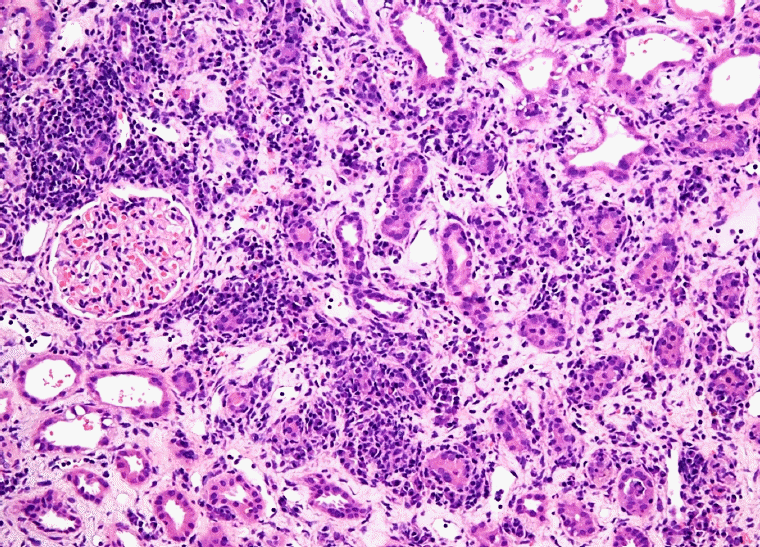

Fig. 5.

Interstitial inflammatory infiltrate composed of plasma cells, lymphocytes and eosinophils with tubular atrophy (×100, hematoxylin and eosin).